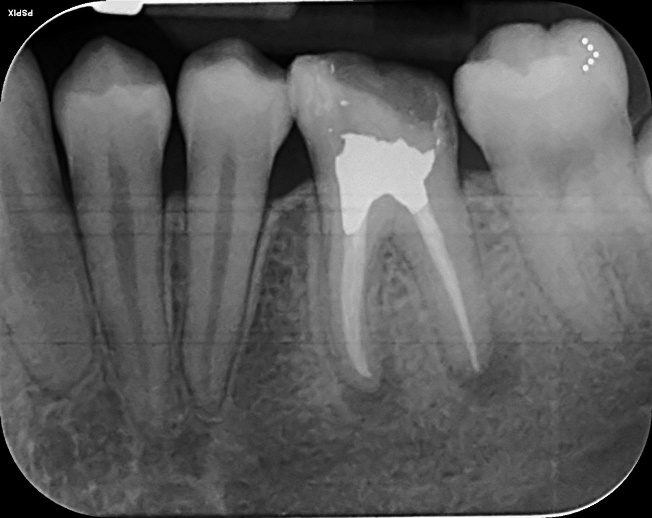

Upper Premolar curved root Primary root canal treatment